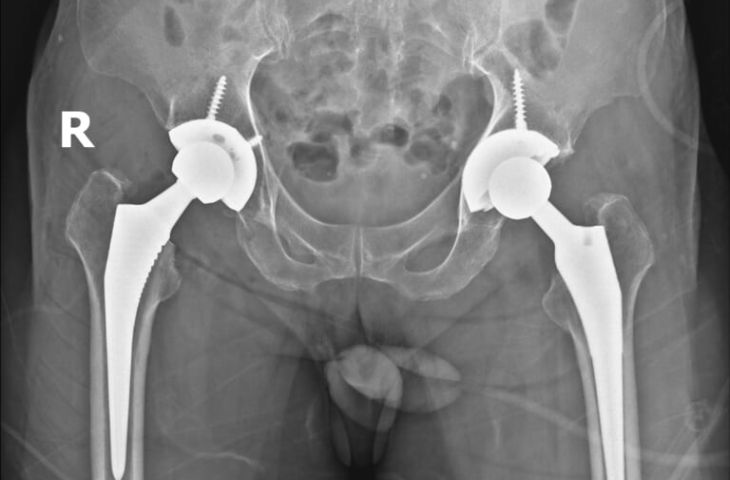

Chụp X-quang: Đây là phương pháp đầu tiên được thực hiện, giúp phát hiện những bất thường của khớp háng, bao gồm:

Chụp X-quang cho ra hình ảnh thoái hóa khớp háng sau khi được phẫu thuật